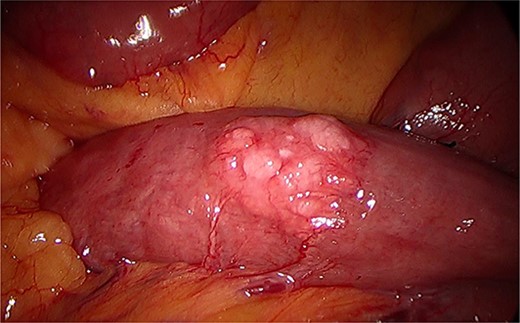

During a thorough inspection of the small bowel in its entirety, a yellow, lobulated oblong lump on the serosa of proximal jejunum was found (Fig. 1). A segment of small bowel including the lesion was resected and sent for histology. The small bowel was re-joined with a stapled anastomosis. Histopathological examination of the lesion revealed a 16 × 13 mm white, serosal nodularity (Fig. 1a). The underlying jejunal mucosa was normal (Fig. 2a). Histological sections were consistent with ectopic pancreatic tissue; they exhibited numerous acinar type glands associated with occasional islet of Langerhans, centred around a main pancreatic duct (Fig. 3). Some of the acinar units show gland drop out, fibrosis, atrophy, and scattered chronic inflammation, indicative of past and chronic pancreatitis (Fig. 4). Microscopically, the EP involved the submucosa and was abutting the serosa. No malignancy was present.

Intraoperative image during laparoscopy visualizing ectopic pancreas on serosa of the jejunum.

(a). Serosal surface of bowel. 16 mm white nodule noted on serosal surface. (b) Luminal surface of bowel. No abnormality seen macroscopically.